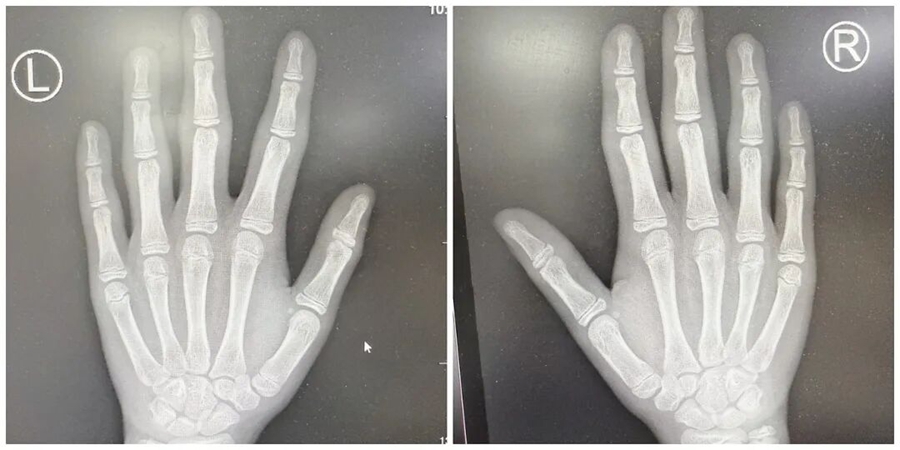

接诊医生肾脏免疫科副主任王一冰发现,小烨的情况有些特殊:他双手的 6 个近端指间关节虽然明显膨大,却不疼不僵,不妨碍日常活动,也没有出现脱发、光过敏、反复口腔溃疡、眼干口干等其他免疫异常症状。

X光片显示,小烨双手指间关节仅有周围软组织肿胀,没有关节间隙狭窄、骨侵蚀、骨膜反应或骨质疏松等异常,这与类风湿关节炎等炎症性关节炎的典型表现有着本质区别;

无系统性炎症指标升高、无自身抗体、无影像学骨关节破坏,且症状局限于手指。综上,小烨最终被明确诊断为厚皮指症。